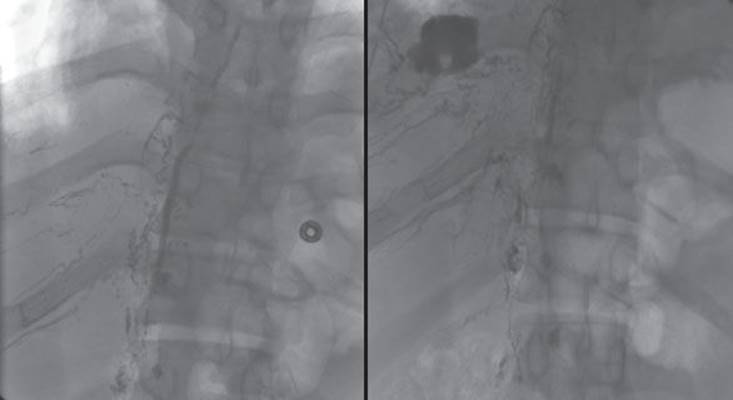

Lymphangiography is a difficult study to perform and its application is limited by local expertise. However, if available, this study can be a useful adjunct to preoperative planning. Lymphangiography can clarify the anatomy of the thoracic duct and potentially identify duplicate or aberrant anatomy. The study may also identify the leak (Fig. 24.2). If the expertise is available, an attempt at embolization of the thoracic duct is reasonable. Lymphangiography is most useful in complicated chyle leaks where the etiology or source of the leak is unclear or in situations where mass ligation fails to control the leak.

Figure 24.2 Lymphangiography can demonstrate the anatomy of the thoracic duct as well as the location of a thoracic duct injury. This lymphangiogram demonstrates the main thoracic duct in its normal anatomical location and a chyle leak into the right pleural space.